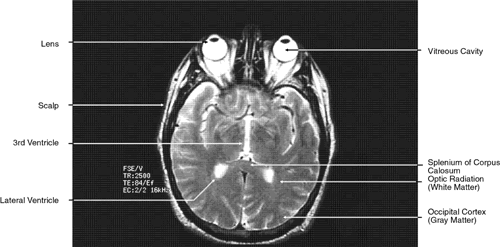

The globe is shown in Figure 12. The orbit and periorbital structures are shown in Figures 13 through 16, and the optic canal is shown in Figures 17 through 26. The cavernous sinus and optic chiasm are shown in Figures 27 and 28, and the posterior visual pathway and cranial nerves are shown in Figures 29 through 33.

Fig. 23. Axial images at the level of midorbit. A. Computed tomography scan. B. T1-weighted magnetic resonance imaging.

Fig. 24. Axial images at the level of superior orbit. A. Computed tomography scan. B. T1-weighted magnetic resonance imaging.

Fig. 25. Axial images at the level of tendon of the superior oblique. A. Computed tomography scan. B. T1-weighted magnetic resonance imaging.